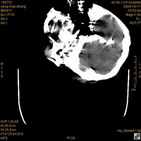

病人杨XX,男,青云街道办事处路踏泉村,住院号51666,CT号:104770。病人因“高血压脑出血”在新泰市人民医院住院治疗5天,治疗效果不佳转入我院,复查CT示左基底节血肿,病人昏迷状态,给予血肿清除术,术后2天复查CT,血肿完全清除,病人恢复好,治疗效果满意。附病人术前术后CT片资料如下。

术后46小时复查CT

术后46小时复查1 术后46小时复查2 术后46小时复查3 术后46小时复查4